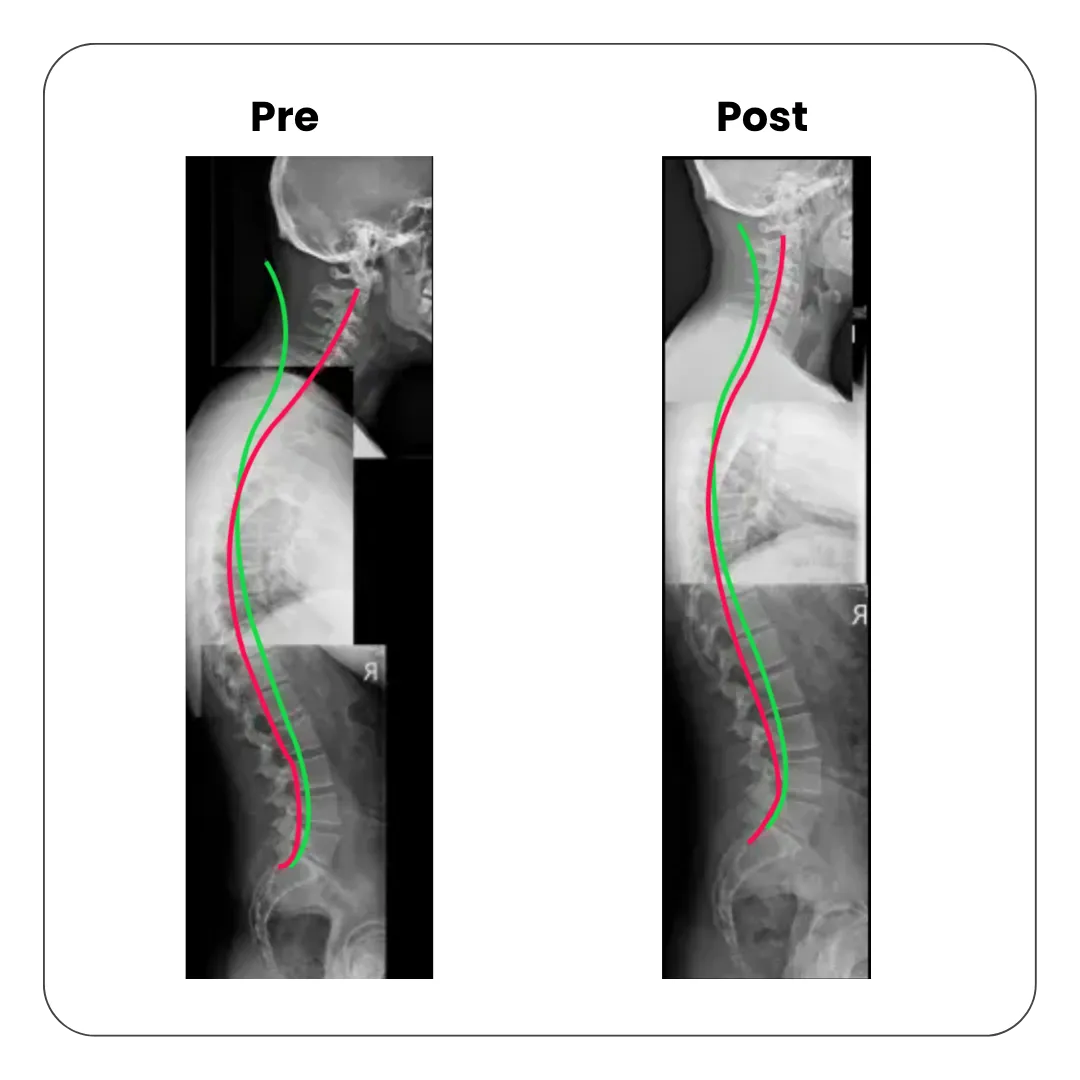

Side view spinal X-rays comparing posture before and after chiropractic posture correction

Pre and Post treatment X-ray showing improved thoracic spine alignment after posture correction care

Reducing Thoracic Hyperkyphosis

Hunching or excessive curvature in the mid back restricts nerve function, contributes to poor health and promotes early disc degeneration in the spine (wear and tear). We specialise in correcting this condition with a customised spinal corrective care program.

Before and after spinal X-ray showing correction of thoracic hyperkyphosis through chiropractic posture correction treatment